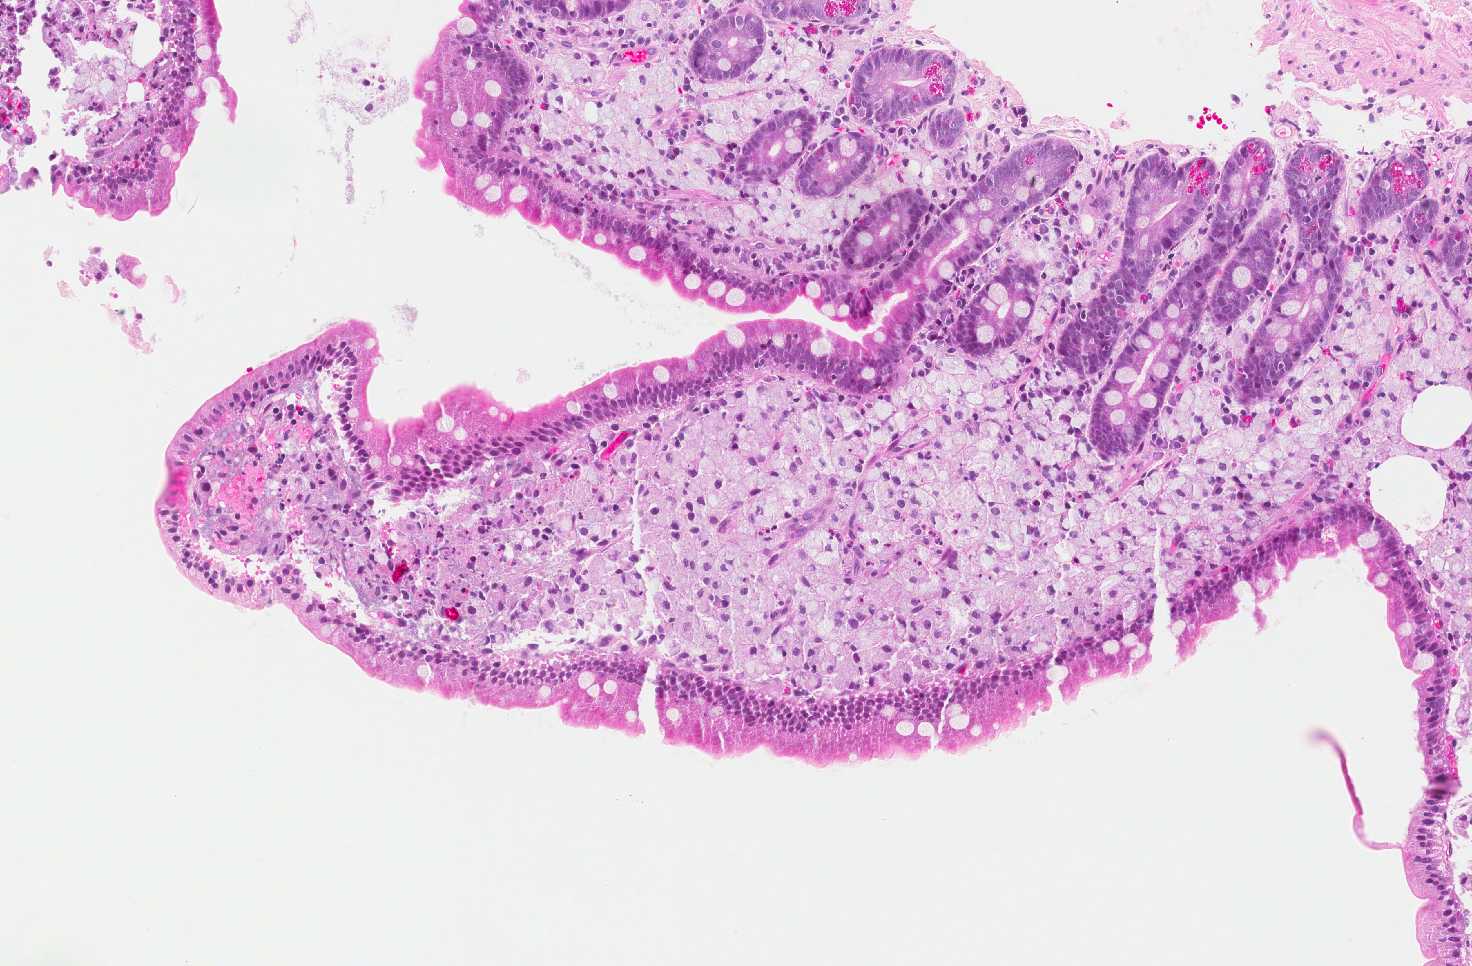

• The lamina propria is filled by foamy histiocytes which expands and blunt the villi (area 1). Note that the foamy histiocytes are not accompanied by significant acute or chronic inflammation.

Area 1: The subepithelial regions of the villi are entirely replaced by foamy histiocytes. Note that the macrophages have foamy cytoplasm, distinct cell border, and rather monotonous, round, and roughly centrally located nuclei. The villi are expaned and blunted by the foamy histiocytes.